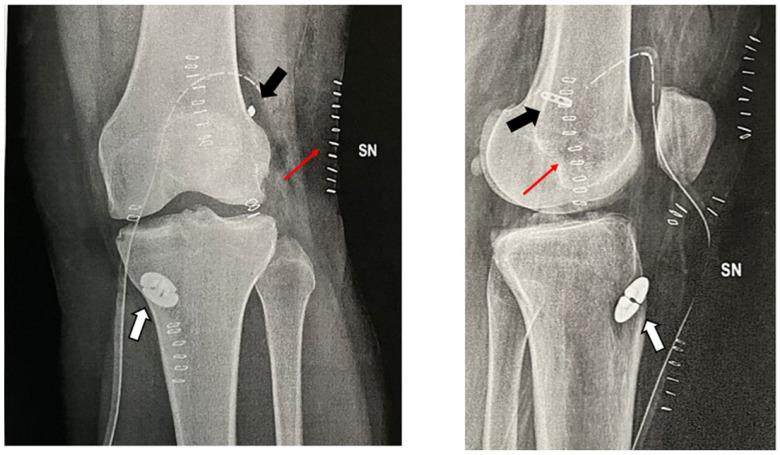

The lateral extra-articular tenodesis (LET) procedure associated with anterior cruciate ligament (ACL) reconstruction can be considered in selected patients to diminish the risk of persistent rotatory instability and achieve a protective effect on the graft. Several techniques have been described in the literature to treat rotatory instability. Usually, a strip of the iliotibial band (ITB) is harvested from its middle while leaving the distal insertion, then passed underneath the lateral collateral ligament and fixed on the lateral aspect of the distal femur with various fixation methods such as staples, screws, anchors or extracortical suspensory devices. Despite their effectiveness, these fixation methods may be associated with complications such as lateral pain, over-constraint and tunnel convergence.

This study presents a detailed surgical description of a new technique to perform an LET during ACL reconstruction with any type of graft fixing the ITB strip with the sutures of the ACL femoral button, comparing its pros and cons in relation to similar techniques found in the literature.

This technique represents a reproducible, easy to learn and inexpensive solution to perform a lateral extra-articular tenodesis associated with an ACL reconstruction using the high-resistance sutures of the femoral button.